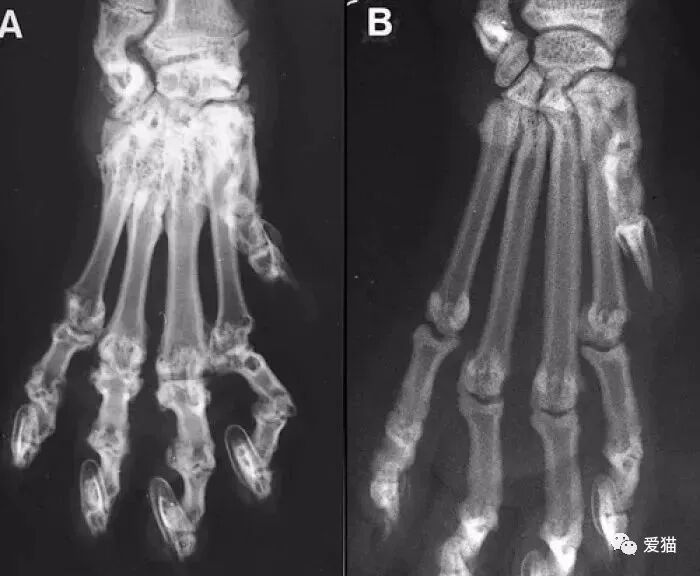

发病的折耳猫,拍的x光照片,骨骼已变形。